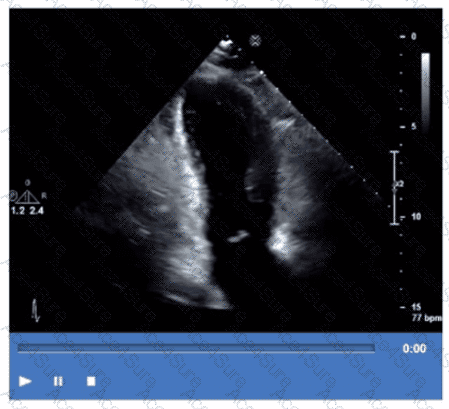

Which coronary artery territory is associated with the wall motion abnormality demonstrated in this video?